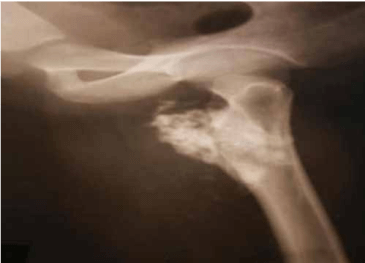

Here we report a 28 years old male present with pain in left hip and thigh due to proximal femoral Osteochondroma. Radiograph shows cauliflower-like mass originating from the left proximal femur. 3D CT scan of left thigh shows compression anterior displacement of femoral vessels near the bifurcation. This patient was treated with surgical en-bloc resection and histopathology was diagnostic of Osteochondroma.

Osteochondroma in the antero-medial aspect of subtrochanteric region of the left femur with origin abutting the lesser trochanter with a large cartilaginous cap causing compression anterior displacement of femoral vessels near the bifurcation.

pre op

Pre op X-Ray